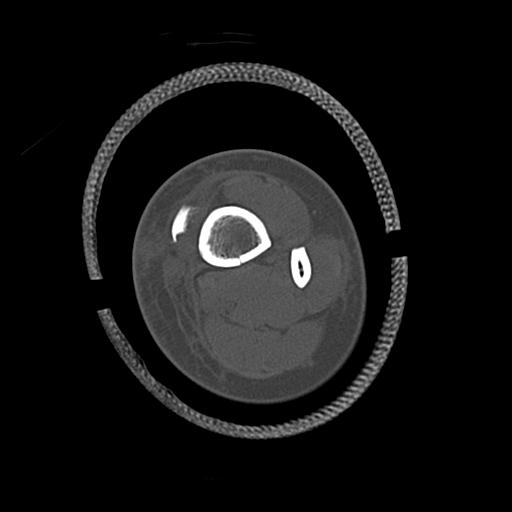

102803 1/12(キウスなし) 1/27 左下腿 4R 30歳女性 左脛骨軸内釘